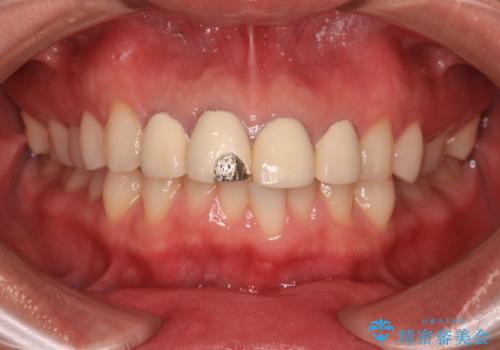

- 以前他院で治療を行った前歯の被せものが欠けてしまい、きれいなセラミックにしたいと来院された患者様です。

人工物のような印象が強くあまり自然とは言えない状態でした。

また被せものと土台の間に隙間があり、適合もよくない状態でした。